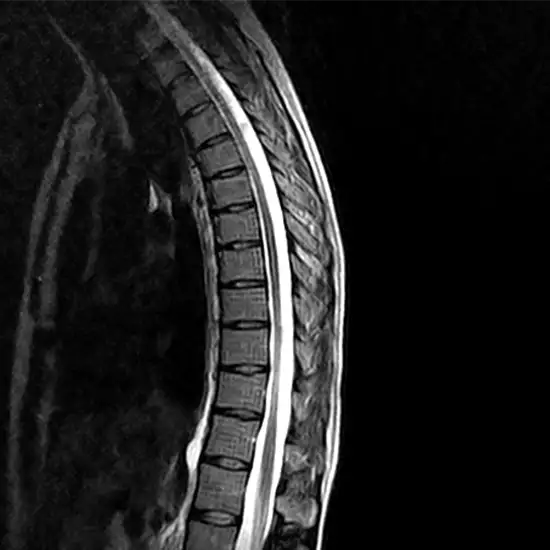

An MRI Scan is a painless, non-invasive scan that obtains a detailed picture of the mid back, lumbar spine, and surrounding soft tissues. MRI machine uses a magnetic field and radio waves to create the pictures and combines them to produce 3D images of the internal structure of the area. This scan is preferred over other scans for the effective detection of abnormalities.

Why is an MRI of the Thoracic Lumbar Spine Done?

• If a patient experiences the symptoms such as lower back pain, mid back pain, stiffness, numbness, tingling sensation, weakness in upper/ lower extremities, etc. doctors recommend this scan to diagnose the source of the pain.

• Abnormal curvature of the spine

• Bulging or herniated discs

• Abnormalities of the spinal cord

• Inflammation of the spinal cord